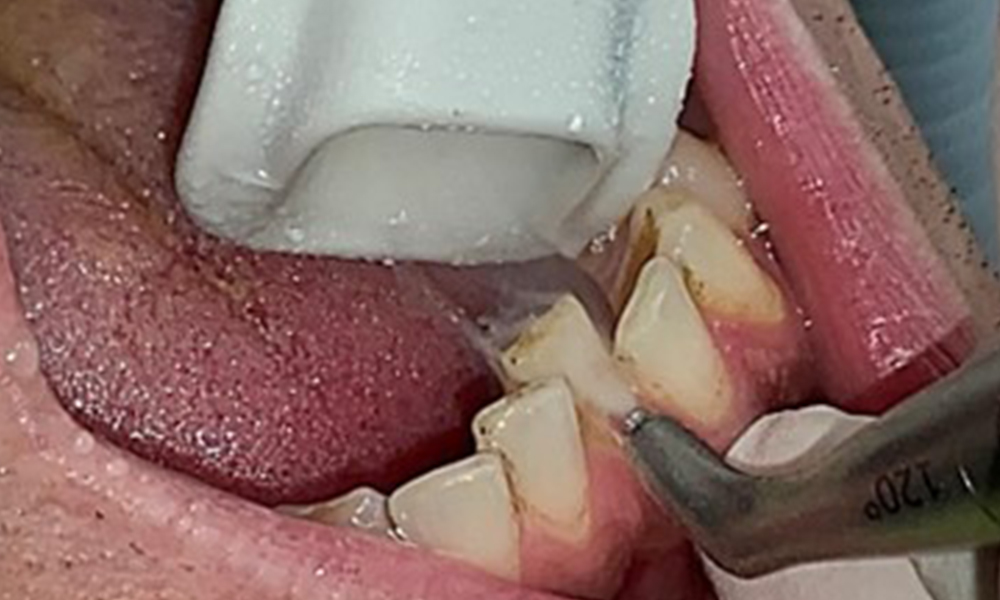

Instruction and motivation are important components of these appointments. Good home-based intraoral hygiene behaviour and understanding are important for patients. Plaque accumulation is particularly evident in the cervical regions (Fig. 8).

The objective would be to control disease risk by removing supragingival and subgingival biofilm. The instruments can be selected based on patient needs. First, calculus and any concretions must be removed using ultrasonic and/or manual instruments (Fig. 10).